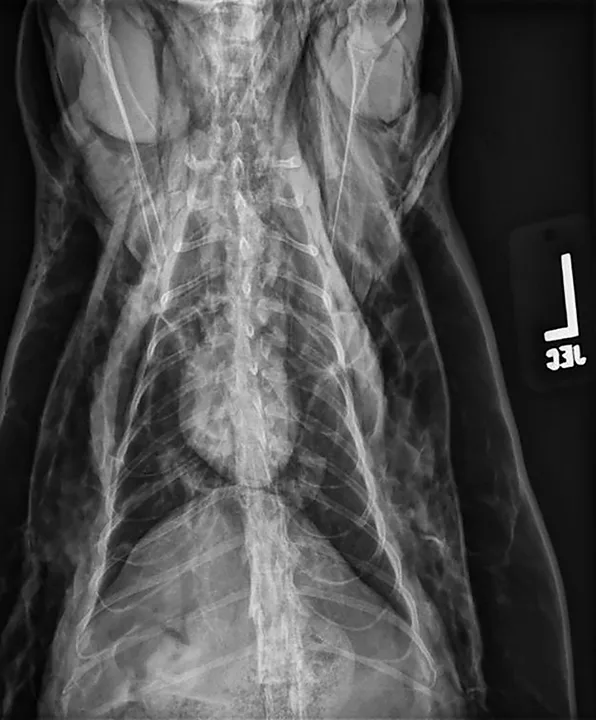

A pneumomediastinum diagnosis is made via thoracic radiography (Figures 1 and 2). Air in the mediastinum outlines the cranial vena cava, dorsal and ventral tracheal walls, esophagus, and aorta. Gas may be present in the retroperitoneal space, cervical fascial planes, and subcutaneous space.2 If an obvious cause of pneumomediastinum is not apparent and the patient is stable, an oropharyngeal examination may be performed with the patient under sedation. Fluoroscopy with iodinated water-soluble contrast or endoscopy can be used to evaluate for esophageal lesions. Airway integrity may be assessed via endoscopy, although small lesions in the trachea may be missed. Advanced imaging (eg, CT) can be helpful in identifying the underlying lesion.

Ventrodorsal view of a patient with severe pneumomediastinum and severe subcutaneous emphysema secondary to a tracheal tear